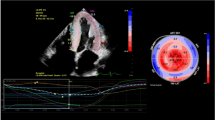

Example of cardiovascular magnetic resonance (CMR) images of AL amyloidosis (upper panel) and ATTRwt (bottom panel) showing cine-images in 4-chamber view in diastole, LGE in 4-chamber view, LGE in short axis as well as corresponding extracellular volume fraction (ECV) maps in a basal short-axis view respectively.